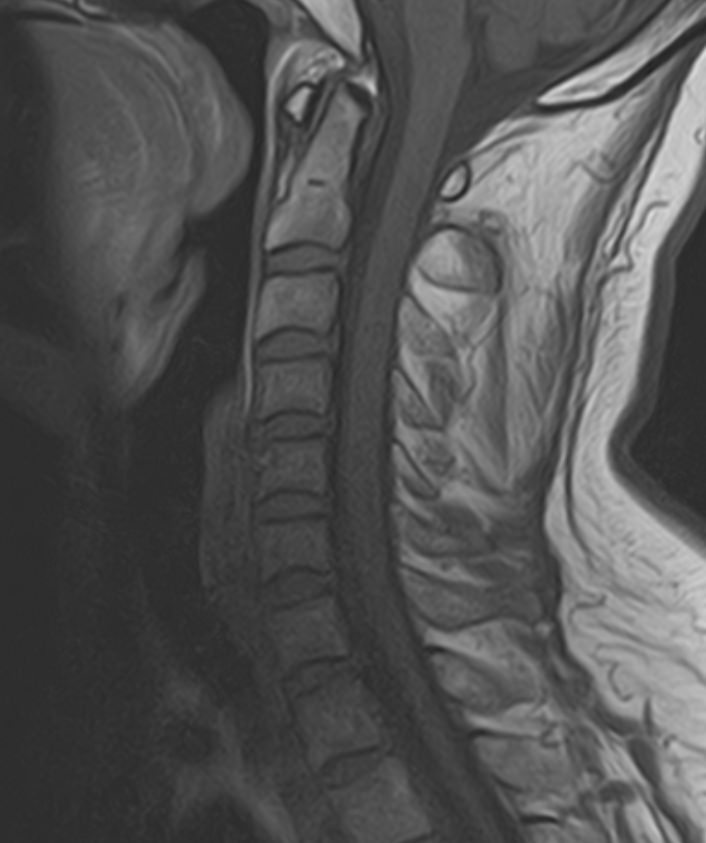

Для диагностики заболеваний ЦНС в клинике «Доступная медицина» проводится комплексное обследование МРТ ЦНС (центральной нервной системы). Клиника укомплектована высокотехнологичным оборудованием, в частности, новейшим 32-канальным высокопольным томографом TOSHIBA VANTAGE TITAN 1,5 Тесла с высокой разрешающей способностью для точной диагностики заболеваний центральной нервной системы.

МРТ центральной нервной системы (ЦНС) (головной мозг + 3 отдела позвоночника)

13 400 / 12 200 руб

Подробнее